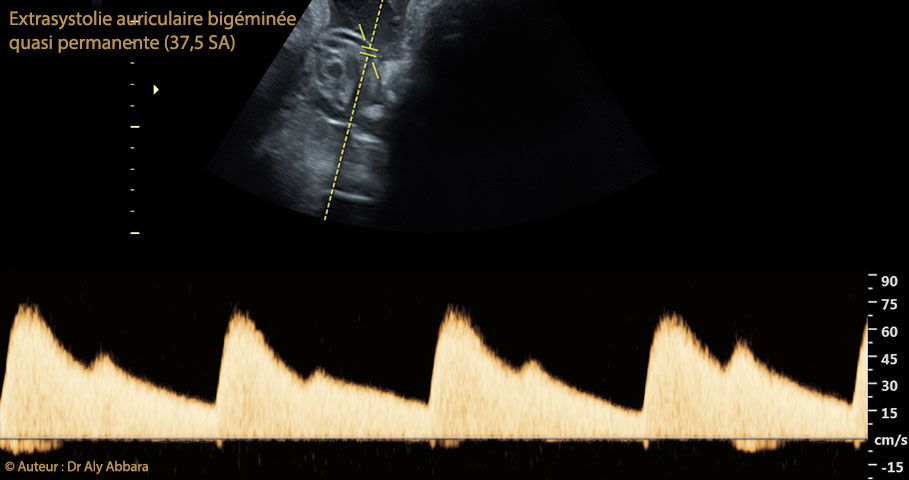

• Vidéo et image échographique à 37,5 SA montrant une arythmie cardiaque fœtale de type " Extrasystolie auriculaire bigéminée quasi permanente ". Pas de signes d'intolérance cardiaque.

• Le Doppler au niveau de l'artère ombilicale confirme le diagnostic d'extrasystolie bigéminée quasi permanente.

• Cette extrasystolie auriculaire se manifestait lors du contrôle du rythme cardiaque foetal (RCF) à l'aide de la tococardiographie par une bradycardie fœtale sévère et permanente à environ 70 battements par minute sachant qu'à l'échographie la fréquence ventriculaire se situait entre 110 et 160 bpm.